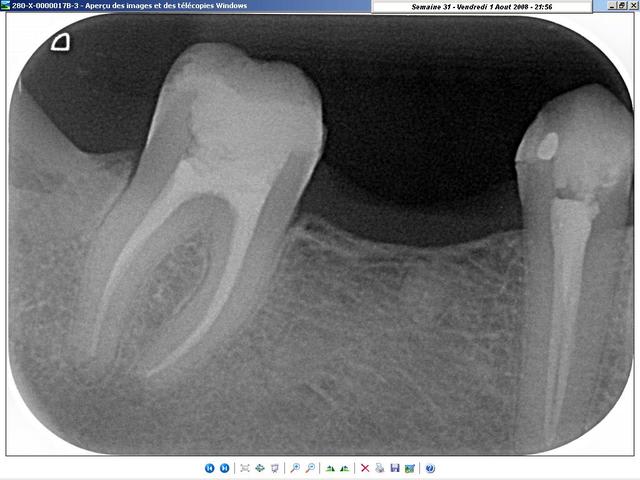

radiologiquement, je ne vois pas trop de différences. A vous de juger.

Les deux cas sont de cette semaine, celui du condenseur, tout frais de cet après-midi; La gutta doit encore être tiède... lol ;-)

sur ce coup, j'étais bien content d'avoir le thermafill (en prêt)!

j'ai préféré faire l'endo plutôt que de galérer à la virer... ^^